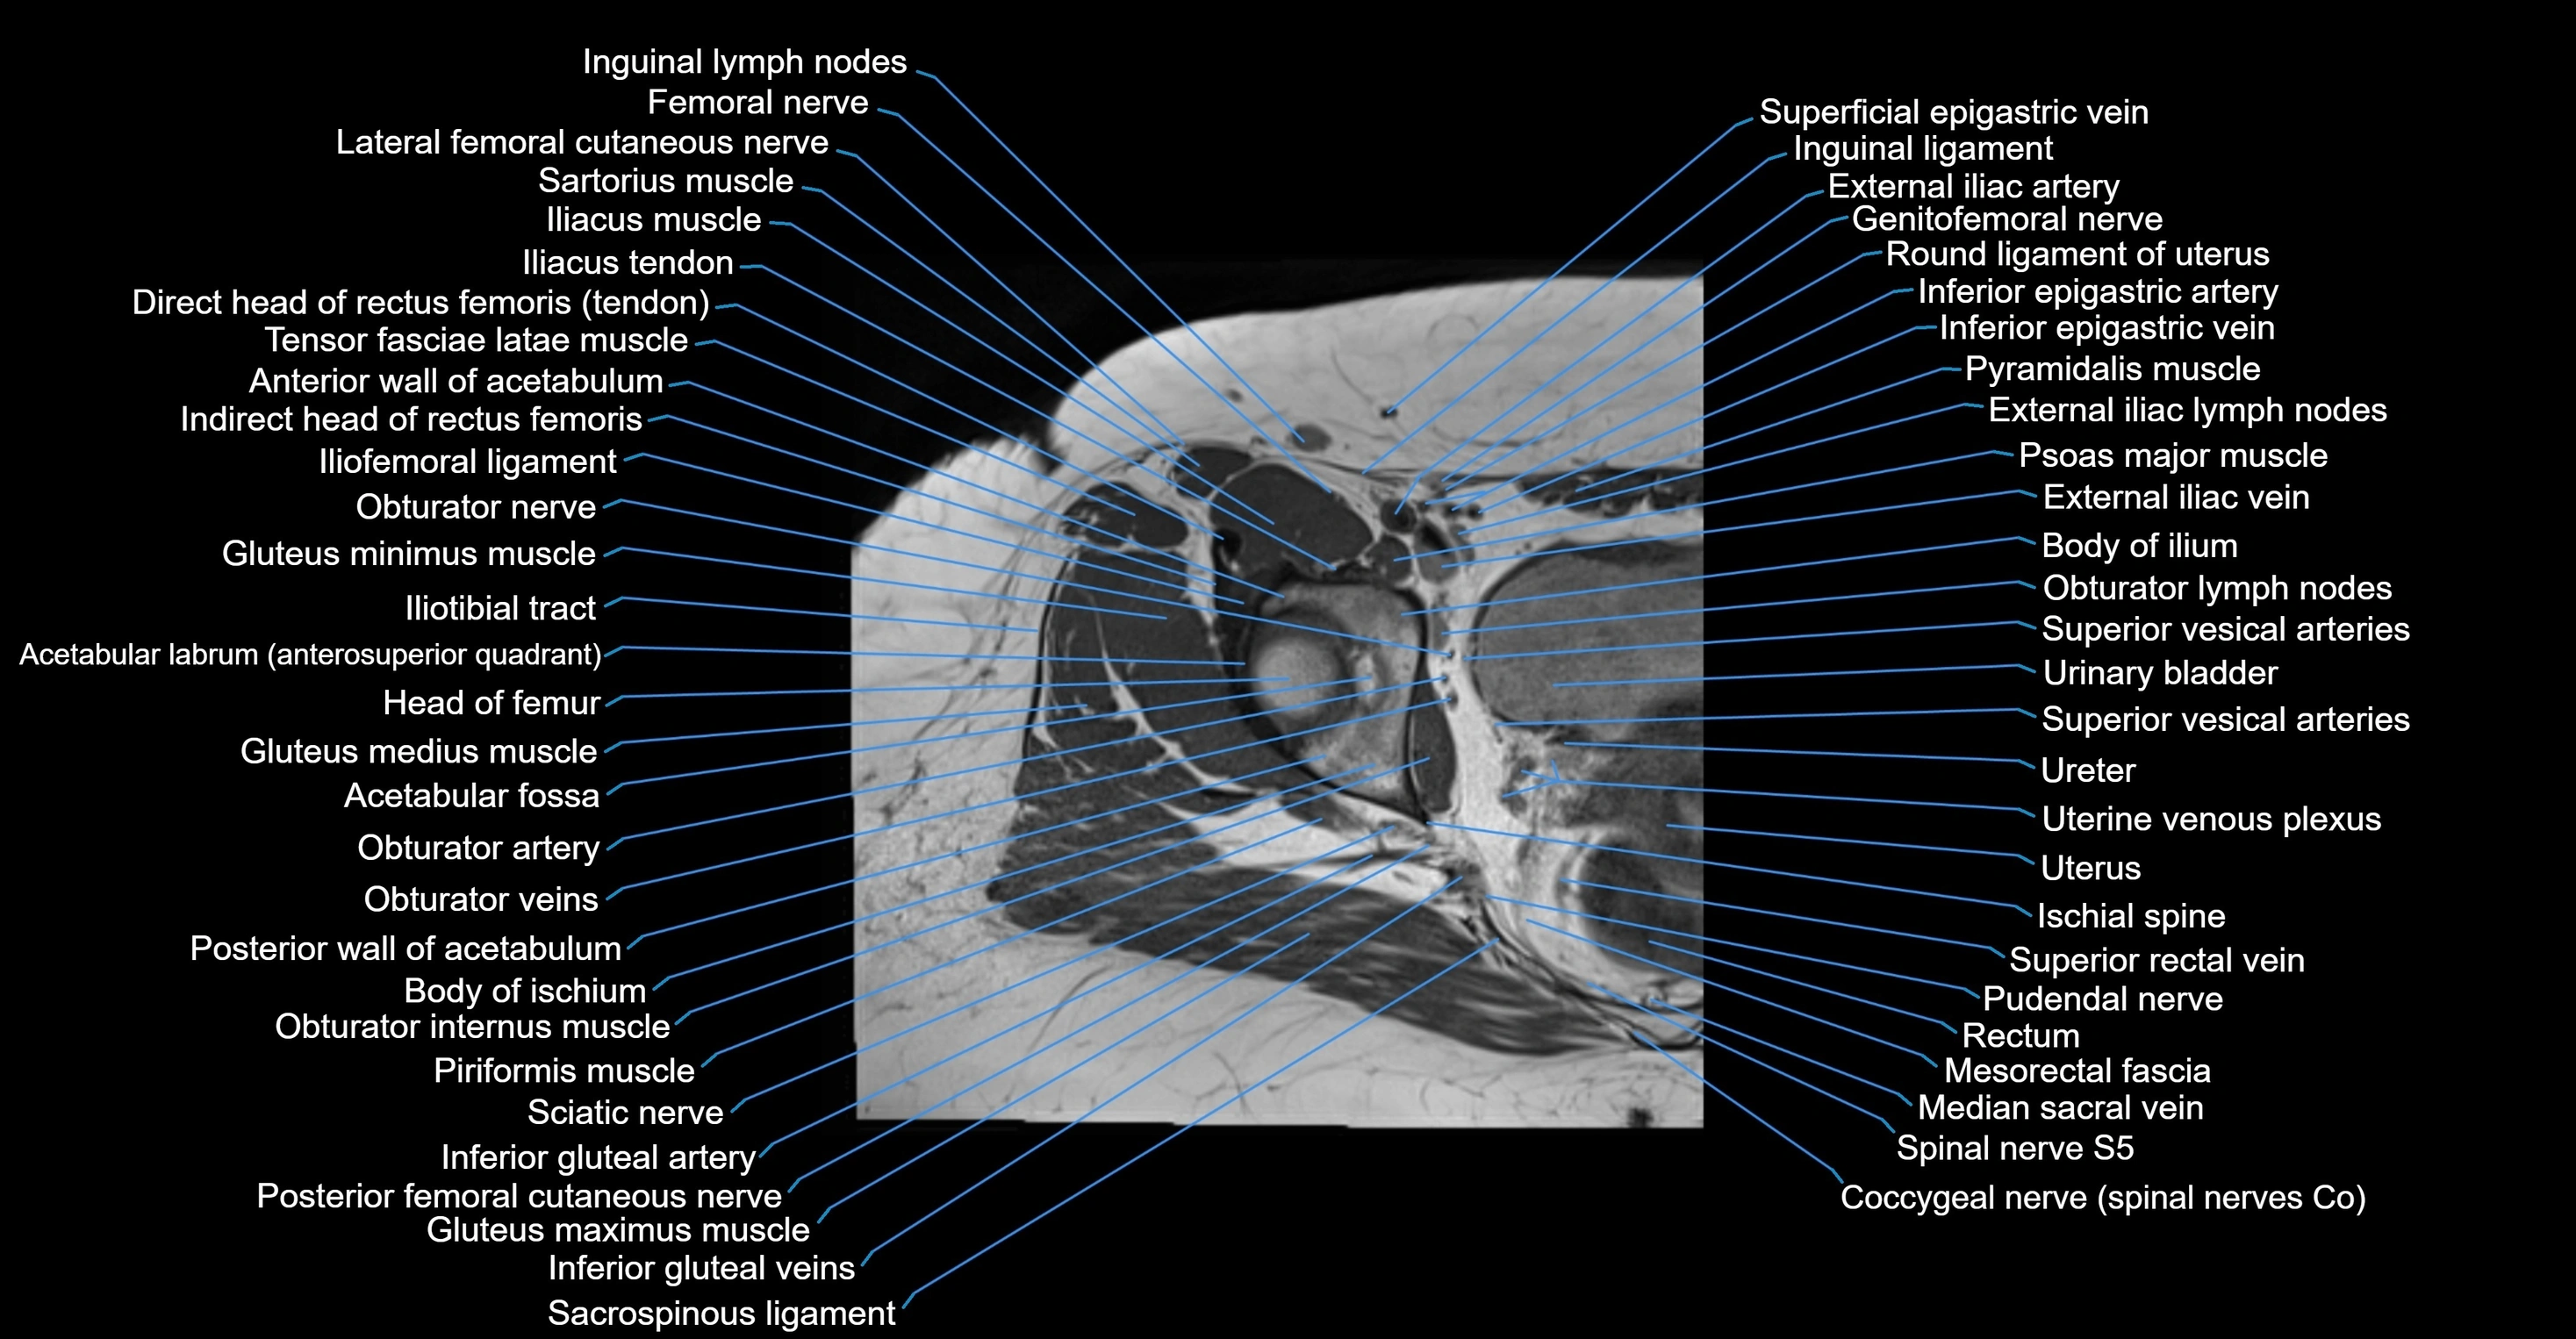

- Acetabular labrum

- External iliac artery

- External iliac vein

- Femoral nerve

- Genitofemoral nerve

- Gluteus maximus muscle

- Gluteus medius muscle

- Gluteus minimus muscle

- Greater trochanter

- Head of femur

- Iliofemoral ligament

- Iliopsoas muscle

- Iliotibial tract

- Inferior epigastric artery

- Inferior epigastric veins

- Inguinal ligament

- Inguinal lymph nodes

- Lateral femoral cutaneous nerve

- Median sacral vein

- Mesorectal fascia

- Obturator internus muscle

- Obturator nerve

- Obturator vein

- Obturator veins

- Posterior femoral cutaneous nerve

- Posterior wall of acetabulum

- Pubococcygeus muscle

- Pudendal nerve

- Pyramidal muscle (pyramidalis muscle)

- Rectum

- Round ligament of uterus

- Sacrospinous ligament

- Spinal nerve S5

- Superior rectal vein

- Tensor fasciae latae muscle

- Urinary bladder

- Uterine venous plexus

- Uterus